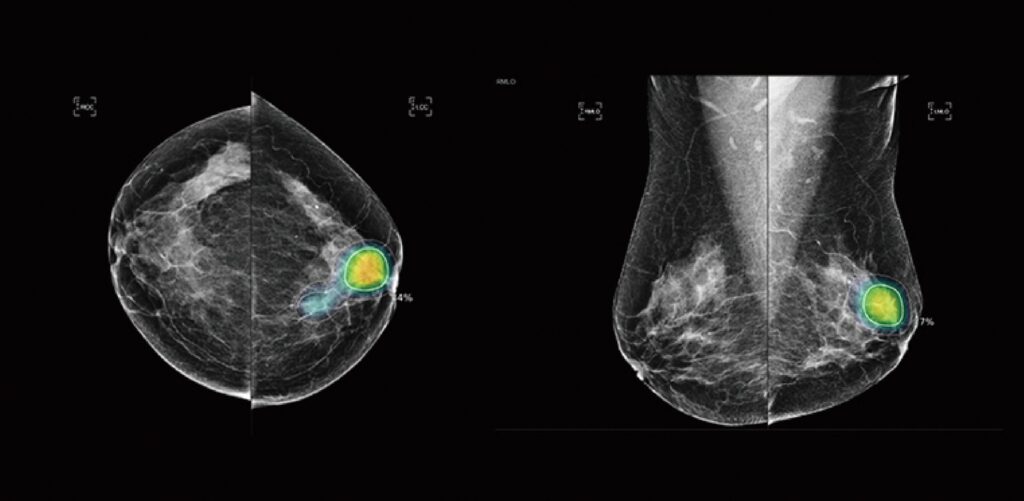

See the SecondReadAI Difference

SecondReadAIÂ review: suspicion of breast cancer detected (indicated by yellow highlighted area).